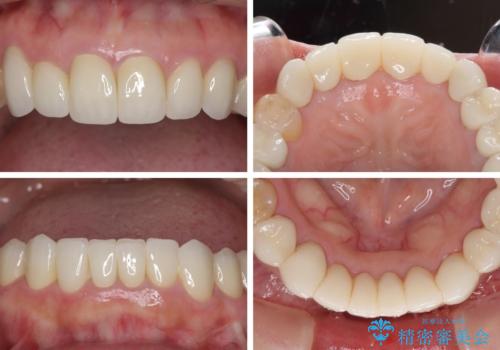

- 下顎の前歯に激痛を覚えて来院された患者様です。

取り急ぎ下顎前歯数歯の根管治療を、銀座しらゆり歯科医院長の林先生にお願いし、それ以外に気になっている、不自然な色調のクラウン、金属部分が見えてブラッシングがしにくいインプラント補綴、口元の突出感、出血のしやすい歯周ポケットなど、全てを解決するための治療を行うこととしました。

期間と費用はかかりましたが、気になっていた部分全てを改善でき、患者様には大変満足していただきました。